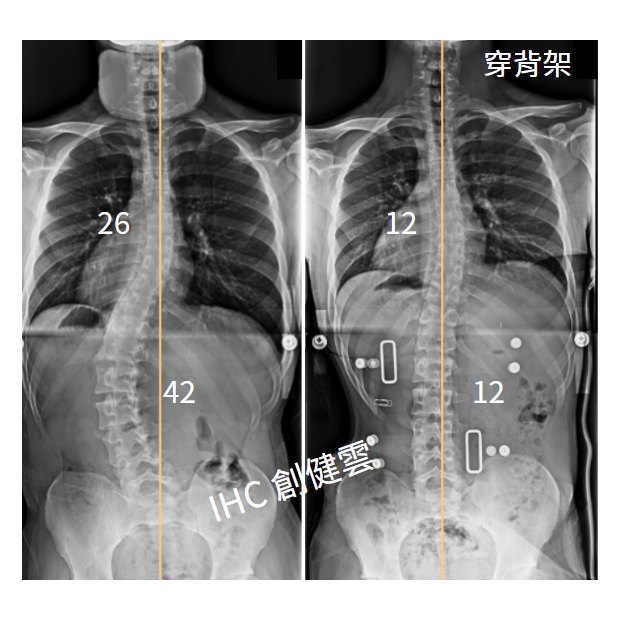

19歲脊椎側彎男生,腰彎42度